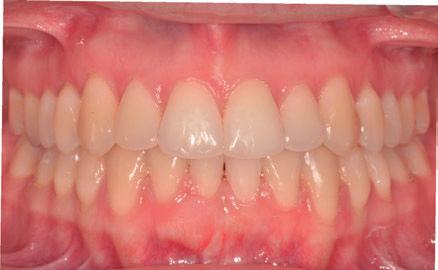

COMPARATIVA INICIO/FIN

Fig.8. Fotos intraoral y de sonrisa inicial (imagen superior) y final (imagen inferior).

Se consiguió cumplir el objetivo principal del tratamiento, que era mejorar la situación periodontal del incisivo y corregir la recesión gingival. Además, con el tratamiento ortodóncico se obtuvo un resultado funcional y estéticamente ideal. PALABRAS CLAVE: recesión gingival, tratamiento orto-perio, injerto conectivo, retención fija.

The main goal of the treatment was achieved, as the recession was successfully corrected. Additionally, with the orthodontic treatment it was obtained a functional and esthetically ideal result.